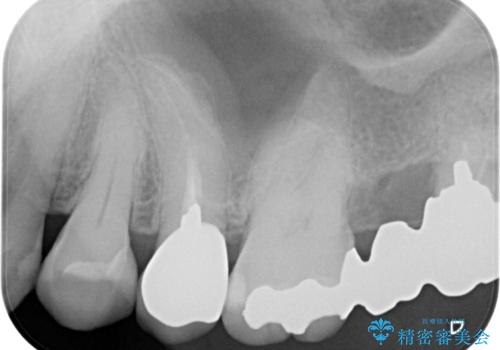

歯根の見えている歯はセラミッククラウンに、詰め物の銀歯が入っている歯はセラミックインレーにて治療を行うこととしました。

笑ったときなど、口を開いたときに目立っていた銀歯や茶色い歯根が気にならなくなり、患者様には大変満足していただけました。